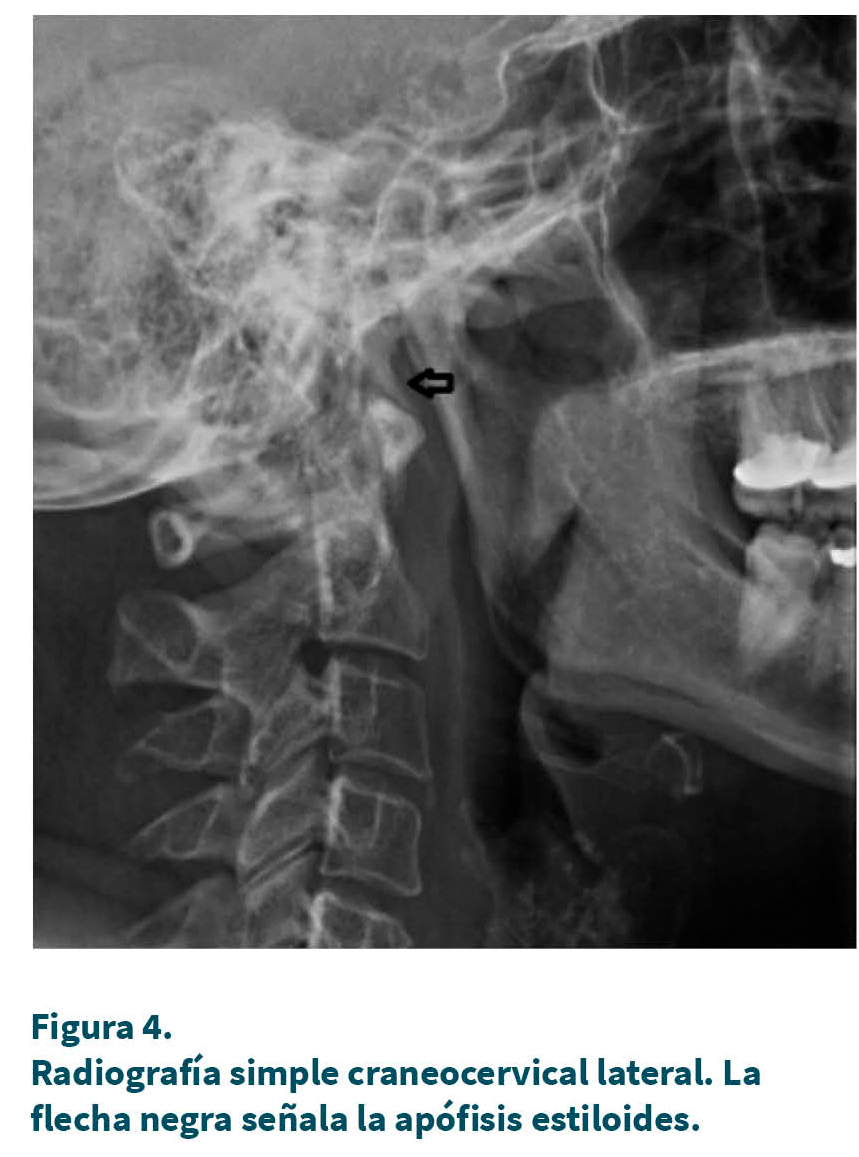

El nervio glosofaríngeo o IX par craneal es un nervio mixto con función sensitiva, motora y visceral, que emerge del bulbo raquídeo y se hace periférico al atravesar el agujero yugular acompañado de los nervios vago y accesorio espinal. Extracranealmente se sitúa posteromedial a la apófisis estiloides (Figuras 1 y 4), entre la vena yugular interna y la arteria carótida interna. Desde aquí alcanza la pared faríngea por la cara exterior del músculo estilofaríngeo, al que proporciona inervación motora. Las ramas principales son el nervio de Jacobson (nervio timpánico) y el nervio de Hering (información visceral del seno carotídeo). El nervio timpánico inerva el oído interno, el oído medio y la trompa de Eustaquio. El nervio glosofaríngeo y su plexo inervan el tercio posterior de la lengua, la orofaringe, el paladar blando y las amígdalas palatinas. Lleva información visceral parasimpática desde los núcleos salivares inferiores, la cual, haciendo relevo en el ganglio ótico, alcanza la glándula parótida (14,19).